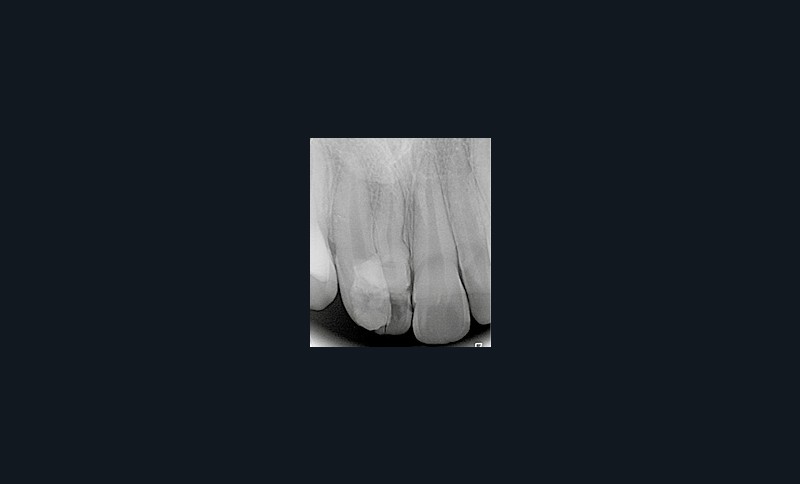

Son incisive centrale supérieure droite (11) présente un défaut de structure amélaire sévère, compromettant une technique restaurative pérenne a minima. L’examen de la panoramique (fig. 1e) et de la radiographie rétroalvéolaire de 11 (fig. 1f) objective une fracture coronaire verticale, ainsi qu’une racine grêle et courbe, peut-être en rapport avec un ancien traumatisme [1]. Le rapport couronne clinique/racine clinique est défavorable.